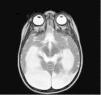

Resonancia magnética cerebral a los 18 meses, extensa afectación crónica secuelar supratentorial, con importante atrofia y encefalomalacia de ambos hemisferios cerebrales, respetando ganglios basales, porciones basales de ambos polos frontales y de ambos lóbulos occipitales. No impresiona de hidrocefalia. Infratentorial se reconoce conservación del tronco encefálico y cerebelo. Charnela cráneo cervical normal. Lesiones cerebrales atribuidas a su prematuridad.